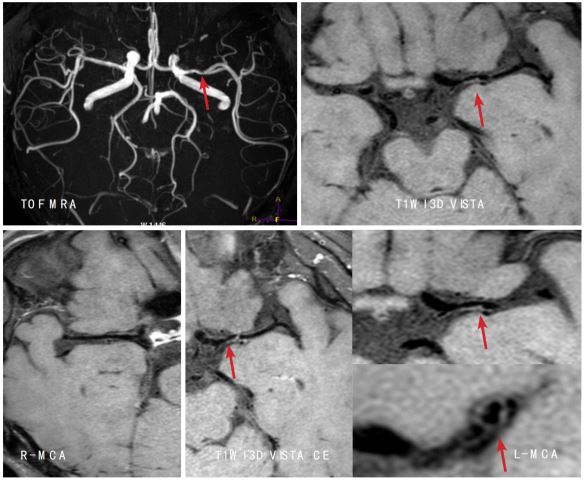

高分辨血管壁成像技术清晰显示椎动脉及基底动脉粥样硬化并斑块形成至管腔狭窄 磁共振高分辨血管壁成像技术显示左侧大脑中动脉 M1 段内血栓致左侧大脑梗塞

磁共振高分辨血管壁成像技术清晰显示左侧大脑中动脉 M1 段炎性增强及管腔狭窄 左侧颈内动脉路外段动脉夹层,可观察到真假腔、内膜片和周围炎性渗出 磁共振大范围高分辨血管壁多对比度成像技术